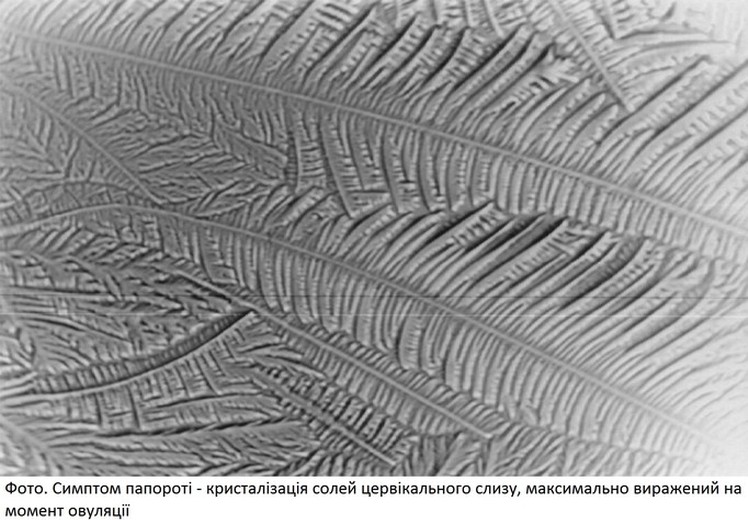

Яєчниковий цикл: фази, тривалість, вплив гормонів. Симптоми овуляції. Утворення жовтого тіла, його значення.

Усі структури шийки матки дуже чутливі до впливу стероїдів. Секреторні клітини слизової оболонки цервікального каналу постійно продукують клейку прозору рідину -

Основний компонент слизу -

Характеристики цервікального слизу (кількість, вміст води, тягучість) зростають відповідно до підвищення секреції естрогенів на момент овуляції. Ці зміни спрямовані на забезпечення умов для фертилізації.

Окрім естрогенів, на шийку матки діють також простагландини і релаксин. Саме ці гормони сприяють розкриттю цервікального каналу в преовуляторний період. У міру підвищення концентрації естрогенів цервікальний епітелій секретує велику кількість рідкого, прозорого, тягучого слизу, багатого на муцин, глікопротеїди, солі, кількість клітинних елементів у ньому в цей час мінімальна. Зовнішнє вічко шийки матки розкривається (максимально на час овуляції), мікрофібрили цервікального слизу розміщуються паралельно, створюються мікроканали, що полегшують міграцію сперміїв. У постовуляторному періоді під впливом прогестерону цервікаль-